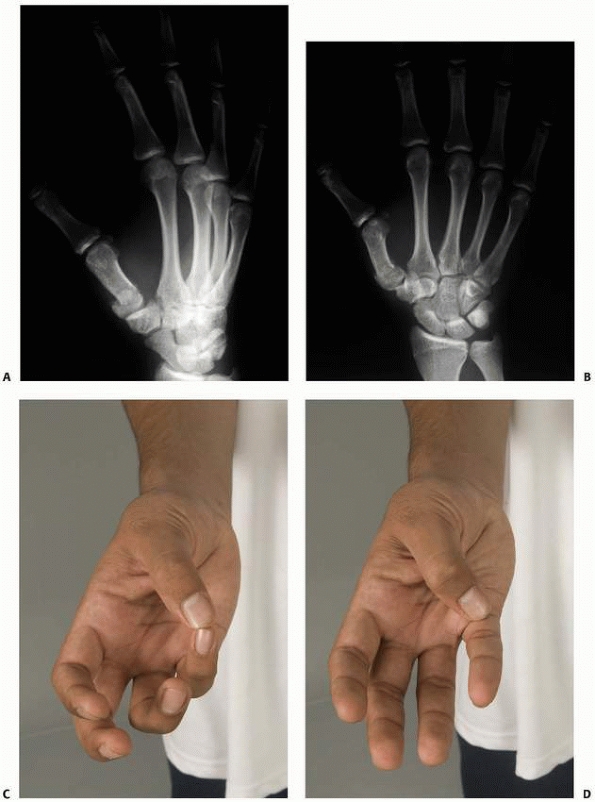

![]() |

FIGURE 8-5

The straight-method of assessing alignment about the MCP joint. The long axes of the metacarpal and proximal phalanx should align, as they do in this normal hand (A). If there is a fracture in the proximal phalanx, as in this patient’s opposite or injured hand (B,C), the axes will not be colinear (arrows). (Courtesy of Robert M. Campbell, Jr., MD.) |